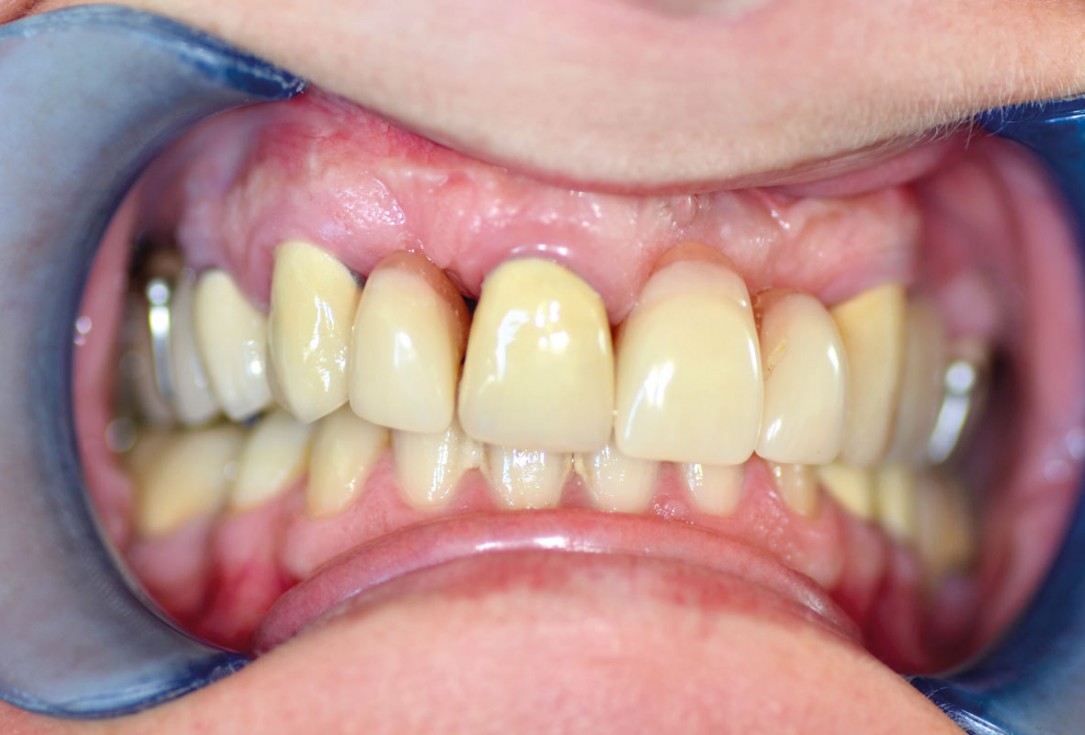

3/14 - Preoperative clinical situationAugmentation in the aesthetic zone with maxgraft® bonebuilder – PD Dr. Dr. F. Kloss

4/14 - Preoperative clinical situation: bone defects in the aesthetic zoneAugmentation in the aesthetic zone with maxgraft® bonebuilder – PD Dr. Dr. F. Kloss